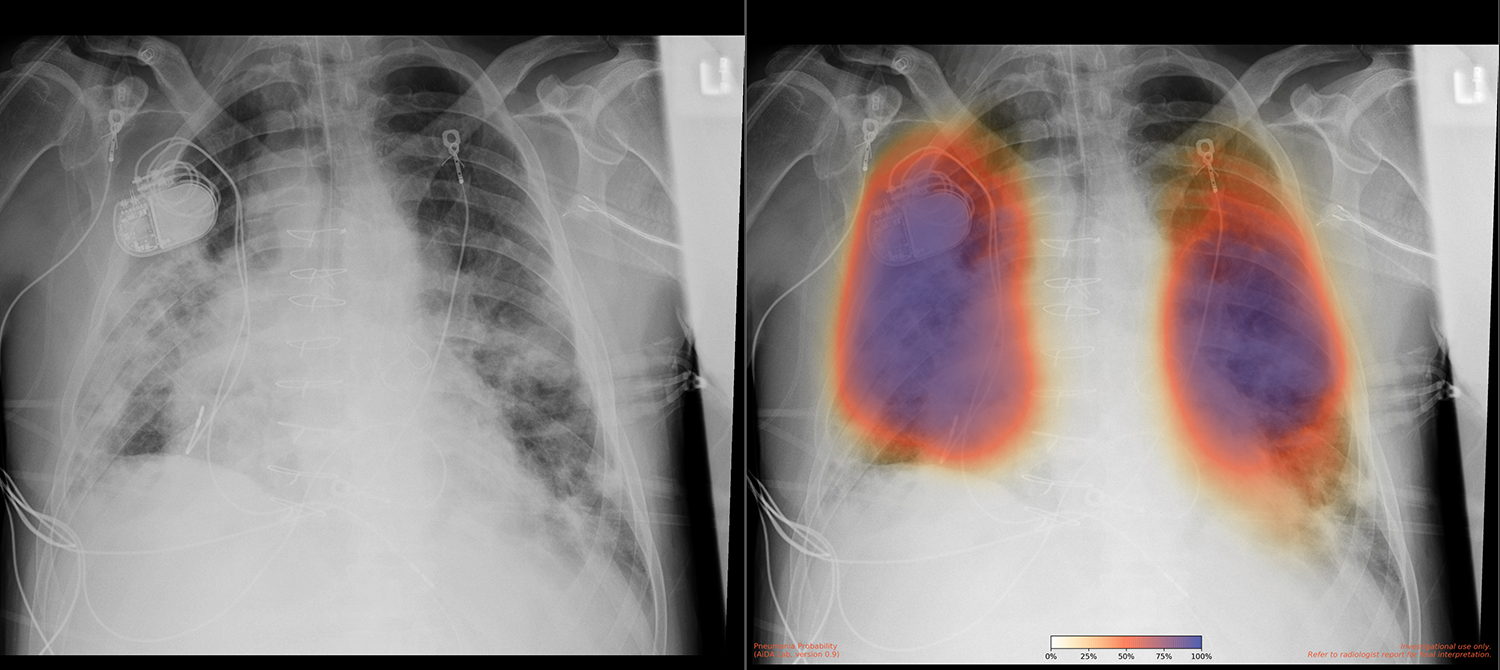

UC San Diego Health is among the top 15 research universities worldwide. The UC San Diego School of Medicine conducts hundreds of clinical trials each year, and the UCSD Health Services Research Center specializes in the collection and analysis of health outcomes data to support research. In 2018, a team from UC San Diego Health, led by Dr. Albert Hsiao, associate professor of radiology at the UC San Diego School of Medicine, developed a way to use machine learning to detect pneumonia in X-ray images. “We created a probability map with color coding that indicated how uncertain or certain a pneumonia was,” says Dr. Brian Hurt, a resident physician on Dr. Hsiao’s team. According to Dr. Hsiao, “What people typically do is create a model that gives a simple yes or no output, indicating whether it’s pneumonia or not pneumonia. But we felt that producing an image was important to highlight where abnormalities are.” The team published a paper on these results in early 2020.

The goal was to implement a system that could take in X-rays from a clinical setting, run the model on them, and return results quickly to assist with diagnosis. “A lot of models created in labs like ours are potentially promising but not very useful without actually building them into the clinical workflow,” says Dr. Hsiao. Such an implementation would potentially affect the diagnosis, treatment, and outcomes of COVID-19 patients. “The findings of COVID-19 pneumonia are basically the same as those of any other viral pneumonia,” says Dr. Hsiao. “The model that Brian trained performs well in this population because it’s a good model for detecting pneumonia in general.” The model was useful in two ways. First, if it detects pneumonia in an X-ray image, it prompts a test or retest in the event of a previous—possibly false—negative test result. Second, in patients with known infection, finding pneumonia on an X-ray could indicate the illness’s severity and prognosis, informing treatments.

The UC San Diego Health research team had already set up the model to take in images and return them with a color-coded overlay. It only needed a cloud solution that could connect to the clinical imaging system to receive the images and output them directly into the patients’ files, making the images convenient for medical professionals to access and view. Because the team had already created HIPAA-compliant environments on AWS, it was able to get the project up and running in a mere 10 days. “The first day it was running on AWS, the model processed around 400 X-rays with very few glitches,” says Dr. Hogarth. In the next 6 months after implementation, the model processed over 65,000 X-rays, each in 3–4 minutes.

A recent paper published by the Journal of the American College of Emergency Physicians Open indicated that implementing this model has impacted clinical decision-making 20 percent of the time. “There are very few things that we know of that really impact clinical decision-making to that extent,” says Dr. Hsiao. The model’s initial accuracy was 86 percent, and the team will soon deploy an even more accurate version that accounts for pneumonia cases often missed when located behind the heart.